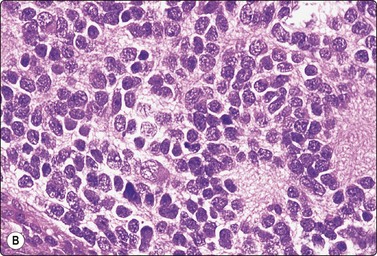

Chromophobe renal cell carcinoma

Criteria for diagnosis

Moderately to highly cellular smears,

Small, loosely cohesive monolayered sheets and single cells with intact cytoplasm,

Mixture of large cells with abundant, pale, flocculent cytoplasm and smaller cells with dense cytoplasm, flocculent,

Thick cell membrane, cytoplasm dense peripherally, pale centrally (halo),

Nuclear grade usually 2, anisokaryosis, binucleation common, small nucleoli,

No stromal material, no necrosis,

CK7+, vimentin−, RCC antigen variable, CD10−, CD117+.

Five percent of RCCs are of the chromophobe type (Figs 12.19 and 12.20). Smears of chromophobe RCC are cellular, showing both single cells and small sheets. There is a conspicuous variation in the size of the cells. Most cells are large with abundant, vacuolated cytoplasm of a flocculent texture. The cytoplasmic density varies; it is dense at the periphery and pale in the center, like a perinuclear halo. Cell membranes are thick. There are also groups of smaller cells with dense cytoplasm, giving an impression of a dual population. There is moderate anisokaryosis, but the nuclear:cytoplasmic ratio is consistently low. Nuclei are moderately hyperchromatic and nucleoli are small. Nuclear grade is mainly 2. The nuclear membranes have been described as irregular and ‘raisinoid’. Binucleation is a common feature, and small nuclear inclusions occur.76-78

image image

Fig. 12.19 Renal cell carcinoma, chromophobe type

Clustered cells, majority with abundant granular and vacuolated cytoplasm, some much smaller cells; moderate anisokaryosis, some cells with small nucleoli. Cytoplasm condensed peripherally, perinuclear pale area, best seen in Pap (A, MGG; B, Pap, HP).

Fig. 12.20 Renal cell carcinoma, chromophobe type

(A) A dual population of large and smaller cells more obvious in this example (H&E, HP); (B) Corresponding tissue section (H&E, IP).

Renal oncocytoma is the main differential diagnosis in FNB smears. Cells of oncocytoma have dense granular eosinophilic cytoplasm and small bland nuclei of uniform size.79 Immune markers are helpful in this distinction.80,81